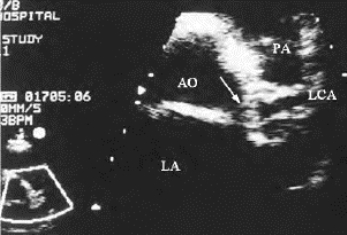

冠状动脉主干及较大分支狭窄时,二维超声显示动脉壁呈不均匀性增厚,或局部有异常回声附着,并凸向管腔,管腔内径变小(图19-9);闭塞时,显示为管腔内充满强弱不等回声。

图19-9 冠状动脉斑块二维超声图

左主干开口处斑块形成(箭头)